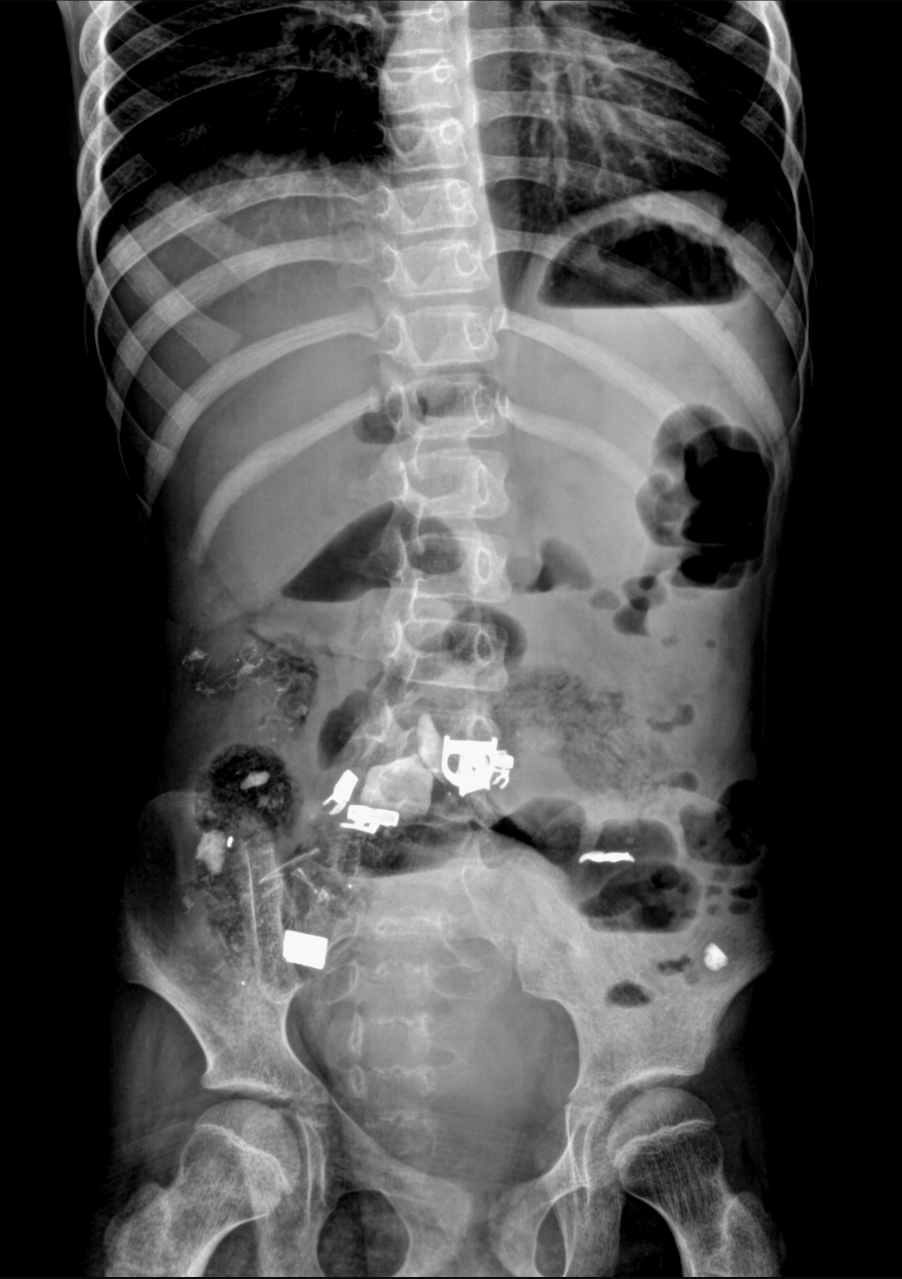

Множество инородных предметов извлекли врачи Жанаозена из кишечника 12-летней девочки

Из брюшной полости девочки были извлечены волосы, ручка, скотч. Об этом сообщили в пресс-службе управления здравоохранения Мангистауской области.

Экстренная операция 12-летней девочке, которая страдает задержкой психического развития (ЗПР) и детским церебральным параличом (ДЦП), была проведена в детской областной больнице Жанаозена.

Девочка поступила в медицинское учреждение в тяжелом состоянии с жалобами на приступообразные боли в животе и многократную рвоту.

- Был проведен рентген органов брюшной полости. Внутри обнаружилось множество инородных тел. Благодаря оперативному вмешательству врачей в ходе операции из кишечника девочки извлекли ручку, скотч, волосы, - сообщили в пресс-службе управления здравоохранения.

Медиками было отмечено, что осложнений в послеоперационном периоде не было. На сегодняшний день ребенок находится в удовлетворительном состоянии.